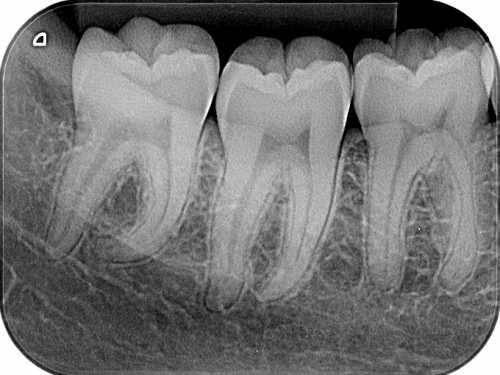

RADIOGRAFIAS

As tomadas radiográficas são feitas para facilitar o diagnóstico. Poderão ser periapicais ou interproximais.

As periapicais mostram o dente, incluindo as raízes e o osso adjacente. Útil nos tratamentos de canal e extrações.

As interproximais mostram a região de contato entre dois dentes, facilitando a detecção de cáries imperceptíveis ao exame clínico.